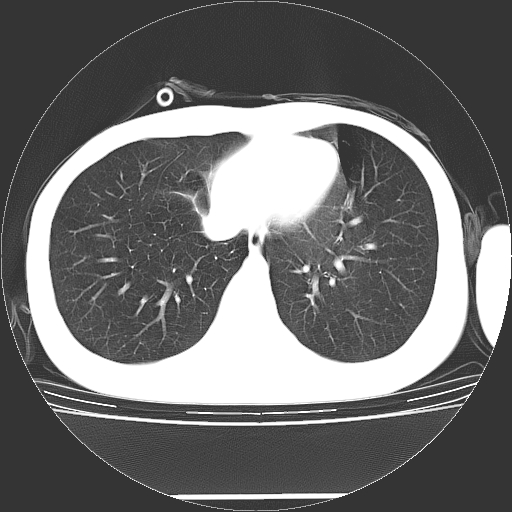

标题: CT19767:男,20岁,右侧气胸行闭式引流术后五天CT检查。 [打印本页]

男,20岁,右侧气胸行闭式引流术后五天ct检查看肺内是否有肺大泡,纵隔窗未见异常,未上传。

1)右侧胸腔闭式引流术后导管留置。2)右肺未见肺大泡。

未见肺大泡,还有微量气体。